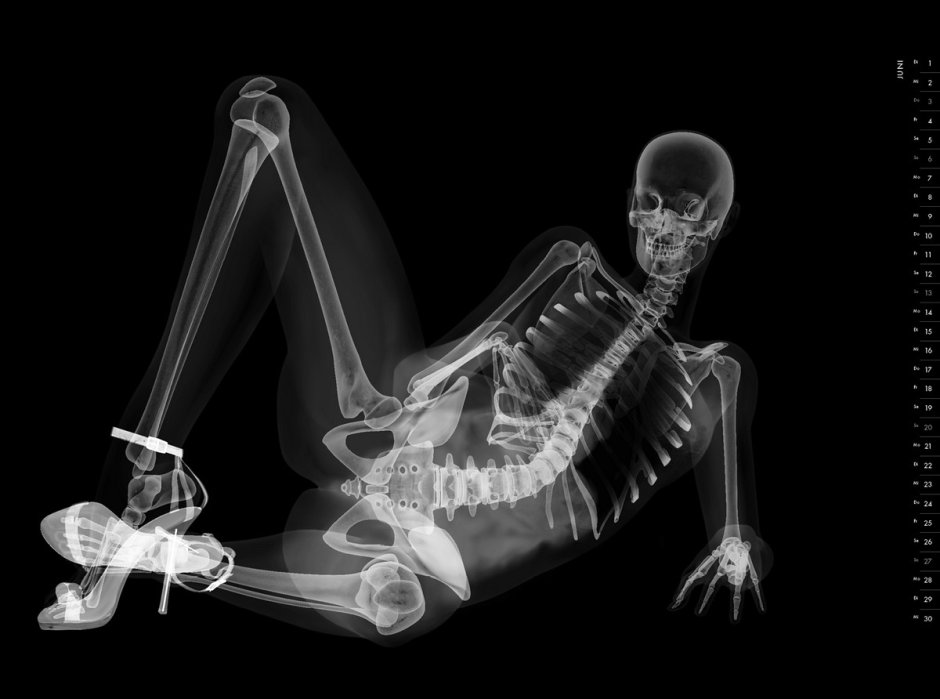

10. Рентгеновские снимки человека

Фото: X-ray рентген скелет

13. Скелет рентген

34. Рентген человека

43. Рентгеновские снимки девушек

61. Рентген снимок